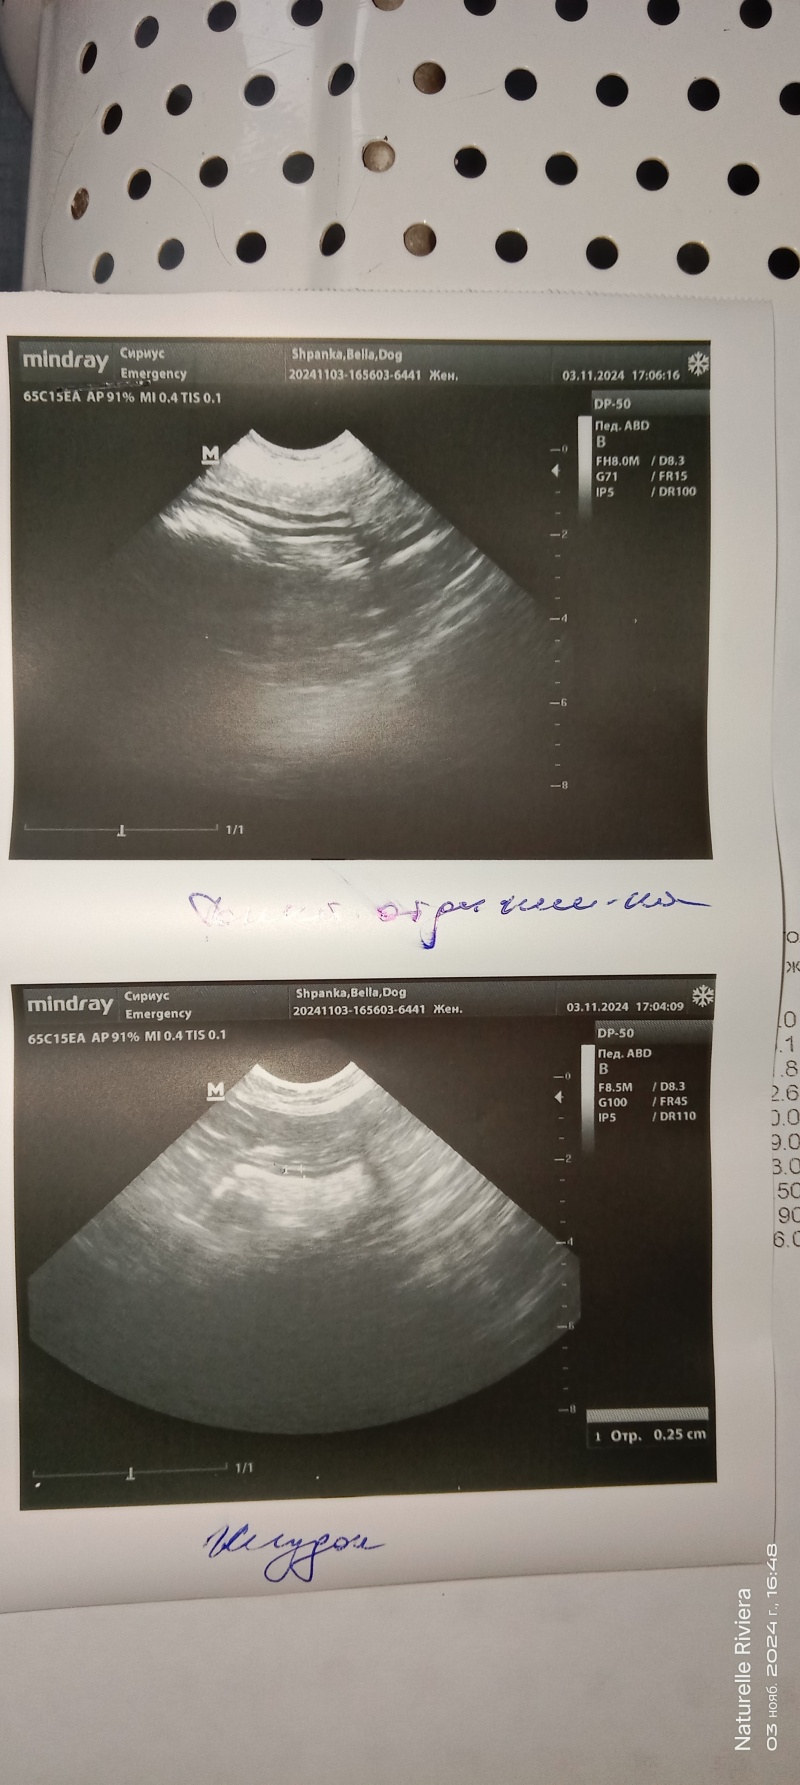

Отменили запись с Масяней по чистке попы, на УЗИ в Интерре всё расписано, поехали в ближайшую в Сириус.

У девоньки t-40C, по УЗИ брюшной полости воспаление желудка и тонкого кишечника. Сделали общий анализ крови, лейкоциты завышены, идёт воспаление, ещё какой то показатель говорит, что снижен иммунитет, а ещё какой то, не помню именно, что у неё аллергия или глистная инвазия.